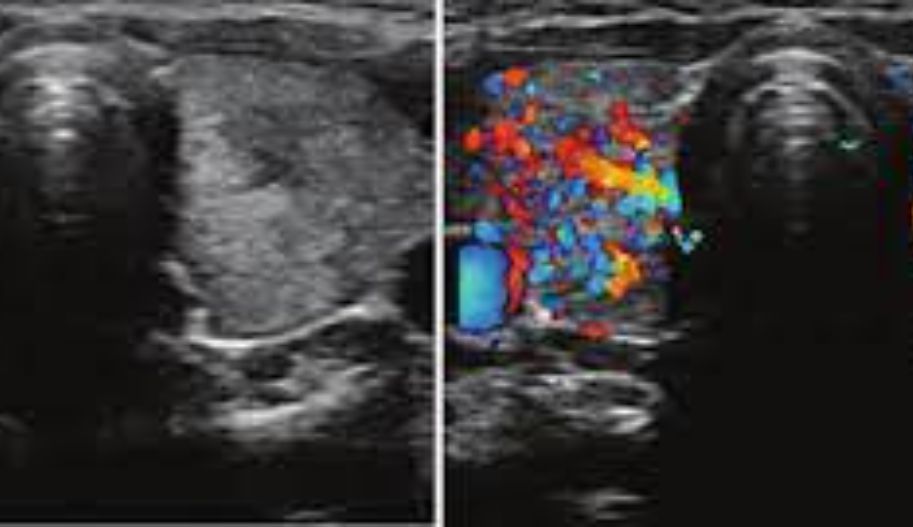

Thyroid Doppler ultrasound can provide valuable information to your doctor, such as whether a thyroid nodule is cystic or solid, the number and location of nodules, the shape and boundaries of the nodules, and the blood flow in the thyroid gland, including the presence of diffuse enlargement known as goiter.

Doppler ultrasounds are fast, painless, and helpful in detecting conditions or early stages of cancers. Many researchers have analyzed the vascularity in thyroid nodules. Studies show that intranodular vascularity is more likely to be detected in malignant nodules than benign ones. However, vascular patterns and degrees overlap significantly between benign and malignant nodules, limiting the use of vascularity as a reliable differentiator.